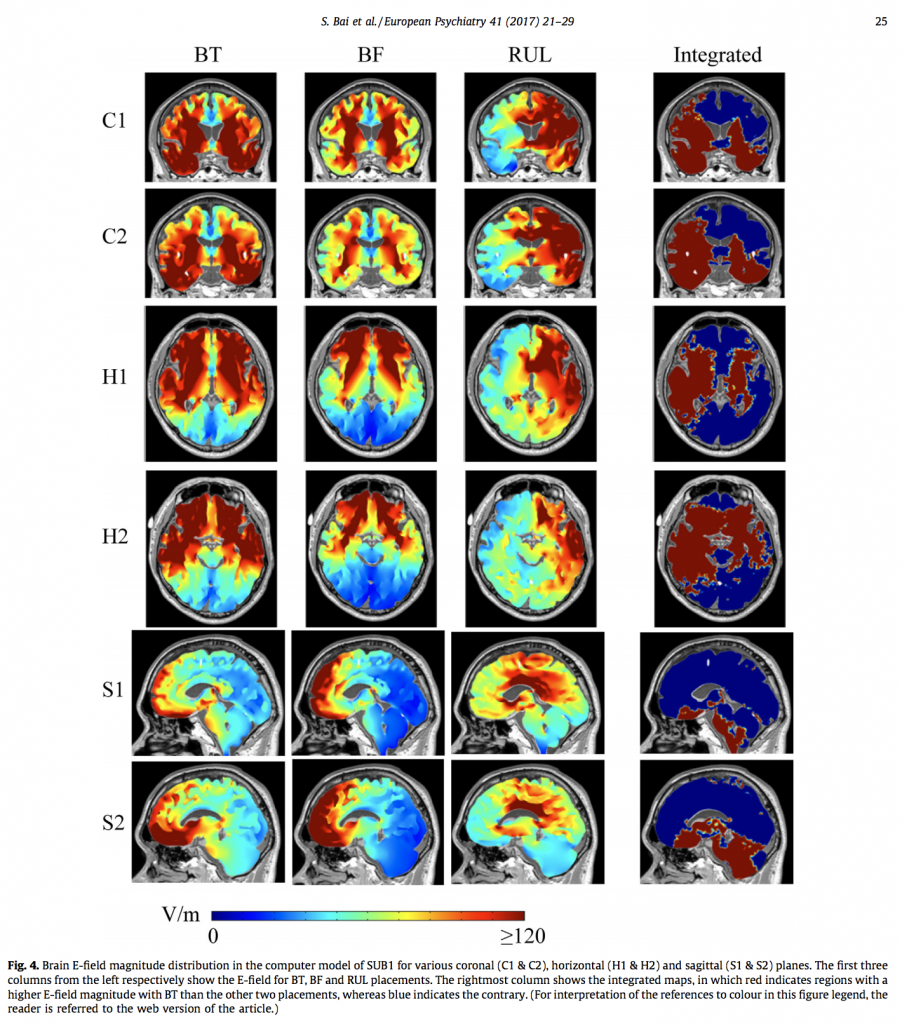

OBJECTIVE: This study used computational modelling to examine regional differences in brain excitation between BT, Bifrontal (BF) and Right Unilateral (RUL) ECT, currently the most clinically-used ECT placements. Specifically, by comparing similarities and differences in current distribution patterns between BT ECT and the other two placements, the study aimed to create an explanatory model of critical brain sites that mediate antidepressant efficacy and sites associated with cognitive, particularly memory, adverse effects.

METHODS: High resolution finite element human head models were generated from MRI scans of three subjects. The models were used to compare differences in activation between the three ECT placements, using subtraction maps.

RESULTS AND CONCLUSION: In this exploratory study on three realistic head models, Bitemporal ECT resulted in greater direct stimulation of deep midline structures and also left temporal and inferior frontal regions. Interpreted in light of existing knowledge on depressive pathophysiology and cognitive neuroanatomy, it is suggested that the former sites are related to efficacy and the latter to cognitive deficits. We hereby propose an approach using binarised subtraction models that can be used to optimise, and even individualise, ECT therapies